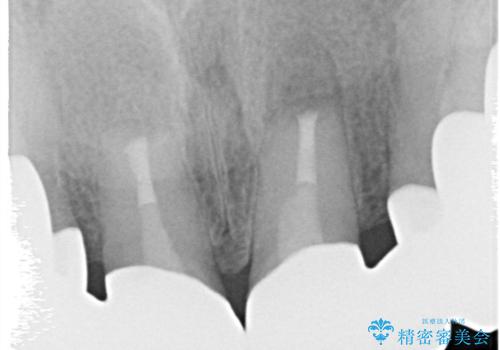

- 前歯の被せもののやりかえを主訴に来院されました。

前歯の歯茎から膿も出ていたため、歯内治療を行なったのち修復を行なっております。

根管治療および外科的歯内療法を行なってから被せものの処置を行なっております。